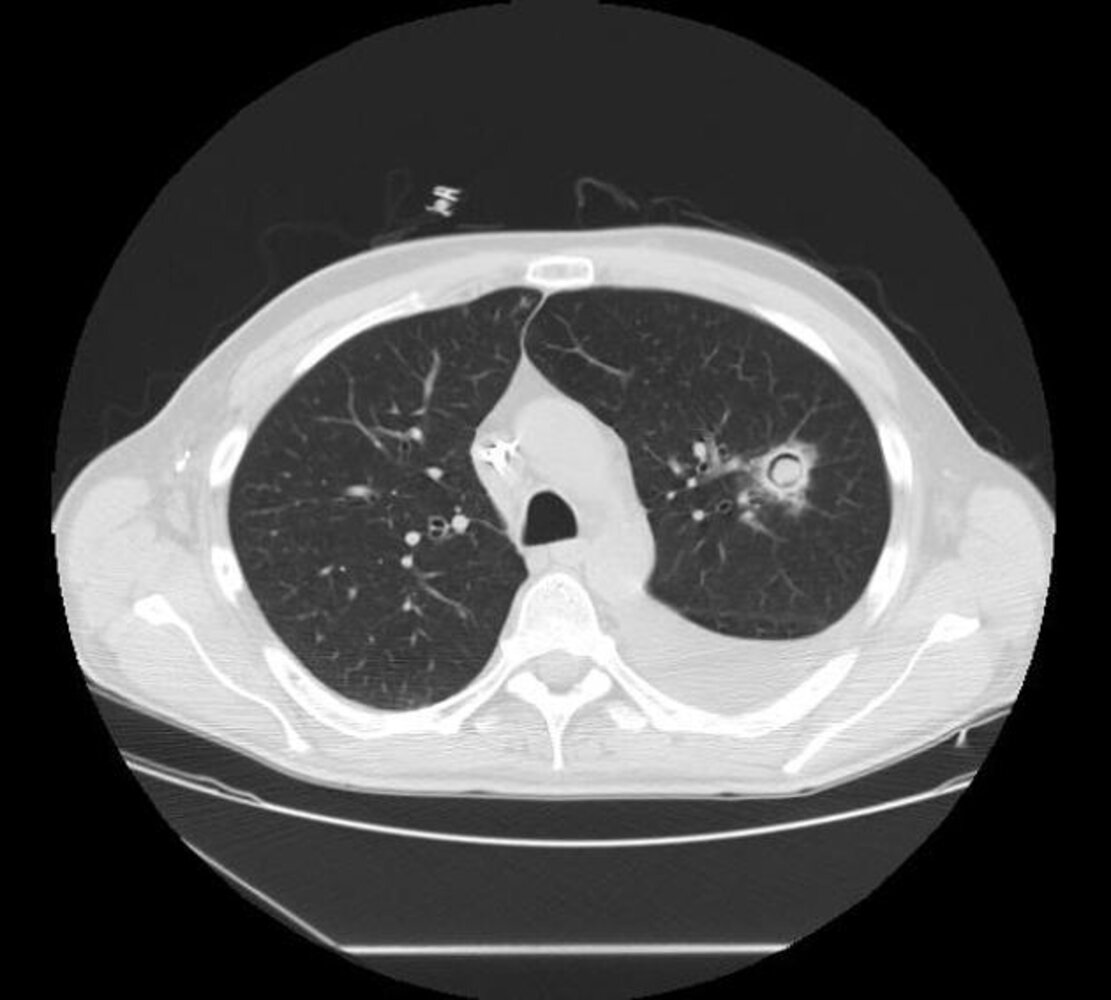

Imaging

Characteristic radiographic findings of Aspergillus infection support the diagnosis.

• HRCT chest without contrast (for all suspected cases): [3][8]

• Air crescent sign: a radiolucent crescent around a radiopaque nodule, characteristic of invasive aspergillosis

• Halo sign: hemorrhagic ground glass opacities around nodules

• Multiple nodules